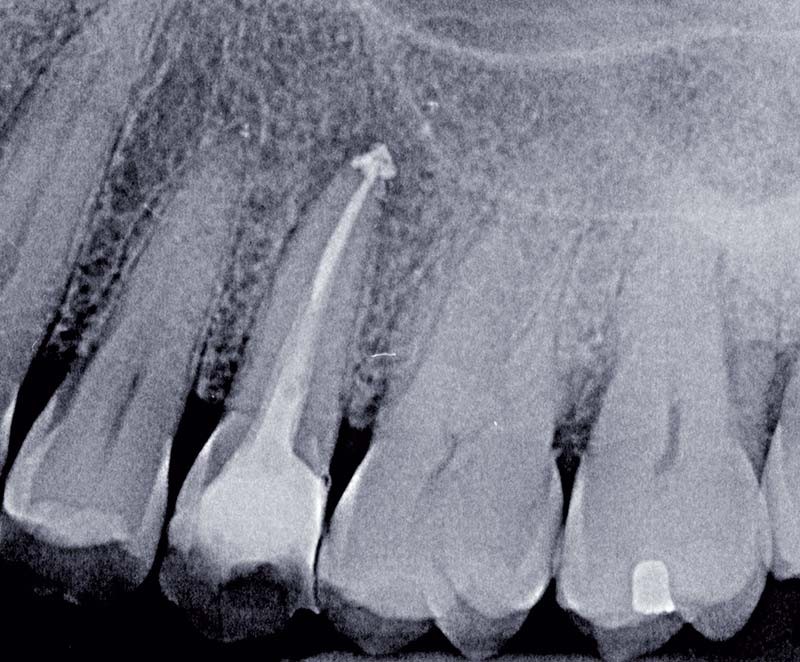

La préservation tissulaire est l’une des préoccupations majeures de la dentisterie actuelle [1]. Mais cette préservation n’est pas limitée à la seule économie des tissus dentaires. Elle prend également en compte la protection de l’organe dentaire. Pendant de nombreuses années, la dent dépulpée était couronnée avec pour seule justification de prévenir la dent de la fracture radiculaire. Le respect des contraintes mécaniques, esthétiques, fonctionnelles et biologiques obligeait, dans le cas de la réalisation

d’une couronne périphérique, à préparer la dent de façon délabrante. La réalisation d’un ancrage radiculaire devenait alors nécessaire, à la suite de la perte de rétention coronaire. Cet ancrage était le talon d’Achille de nos restaurations, responsable de ces fractures radiculaires. Les nombreux progrès réalisés au niveau du collage permettent désormais d’envisager des préparations moins mutilantes et même un renforcement de la structure dentaire [2].